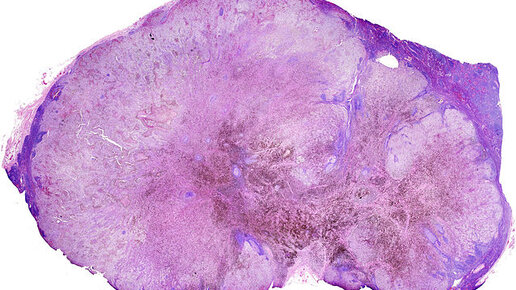

Российские ученые обнаружили, что противораковый препарат дакарбазин защищает часть клеток меланомы от действия химиотерапии. Лекарство переводит клетки в «спящий режим». Меланома — одна из форм рака кожи, обладающая повышенным уровнем опасности для жизни пациента. Каждый год с заболеванием сталкиваются около 200 000 — 300 000 человек, а еще примерно 60 000 человек погибает от развития тяжелых форм новообразований, не поддающихся лечению. Оказалось, что наиболее тяжелые вариации меланомы могут возникать из-за действия дакарбазина на отдельные опухолевые клетки...